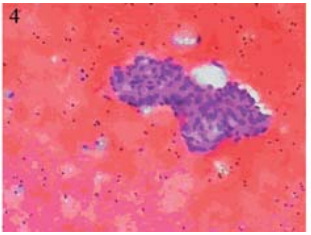

于2012年11月5日在B型超声定位下行肝包膜下 囊性包块穿刺引流,引流液暗红色不凝血,查穿刺 液常规:颜色:暗红色,红细胞计数:150×109/L, 白细胞计数:600×109/L,中性粒细胞70%,淋巴 细胞30%,李凡他试验+,透明度:浑浊。生化: 总蛋白:50.1 g/L,乳酸脱氢酶:1 042 IU/L。肿 瘤指标:CEA:958 ng/ml,CA125:788.2 IU/ml, CA199:>195 9 IU/ml,AFP:5.8ng/ml。脱落细胞 学检查找到癌细胞,见图 4。引流后于2012年11月9 日予顺铂40 mg囊腔内注射,治疗后复查肝脏B型 超声:肝包膜下囊性占位明显缩小,大小约0.8 cm ×0.8 cm,见图 5。

图 4 肝包膜下巨大囊性转移瘤患者脱落细胞学检查 Figure 4 Cytology of huge cystic metastatic tumor of hepatic subcapsular Cancer cells were found |